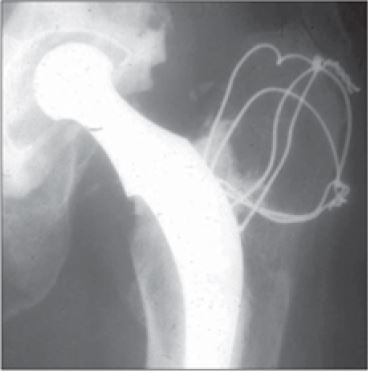

Los remplazos articulares de la cadera datan de 1826, cuando el Dr. John Rea Barthon, ortopedista del Hospital de Pensilvania, llevó a cabo una osteotomía intertrocantérica sin anestesia en tan solo siete minutos en un paciente ( figura 1). Se trataba de un marinero de 21 años de edad con anquilosis de la cadera que inició después de una caída de aproximadamente dos metros de altura mientras se encontraba trabajando en 1825 ( 9, 10, 11).

Pasados 20 días de la intervención, el Dr. Barthon, manipuló y movió la extremidad, por lo cual el foco de la osteotomía se diferenció como tejido fibroso y posteriormente generó seudoartrosis. En el postoperatorio, el paciente recuperó la marcha asistido de un bastón tres meses después de la intervención; sin embargo, pasados seis años, el paciente perdió nuevamente la funcionalidad y el movimiento de la extremidad. A pesar de lo anterior, el Dr. Barthon introdujo un concepto importante y revolucionario en la ortopedia, devolver a un paciente la movilidad de una articulación anquilosada. Este sería el pilar que hoy ha evolucionado hasta artroplastias seguras, exitosas y eficientes ( 9, 10, 11, 12).